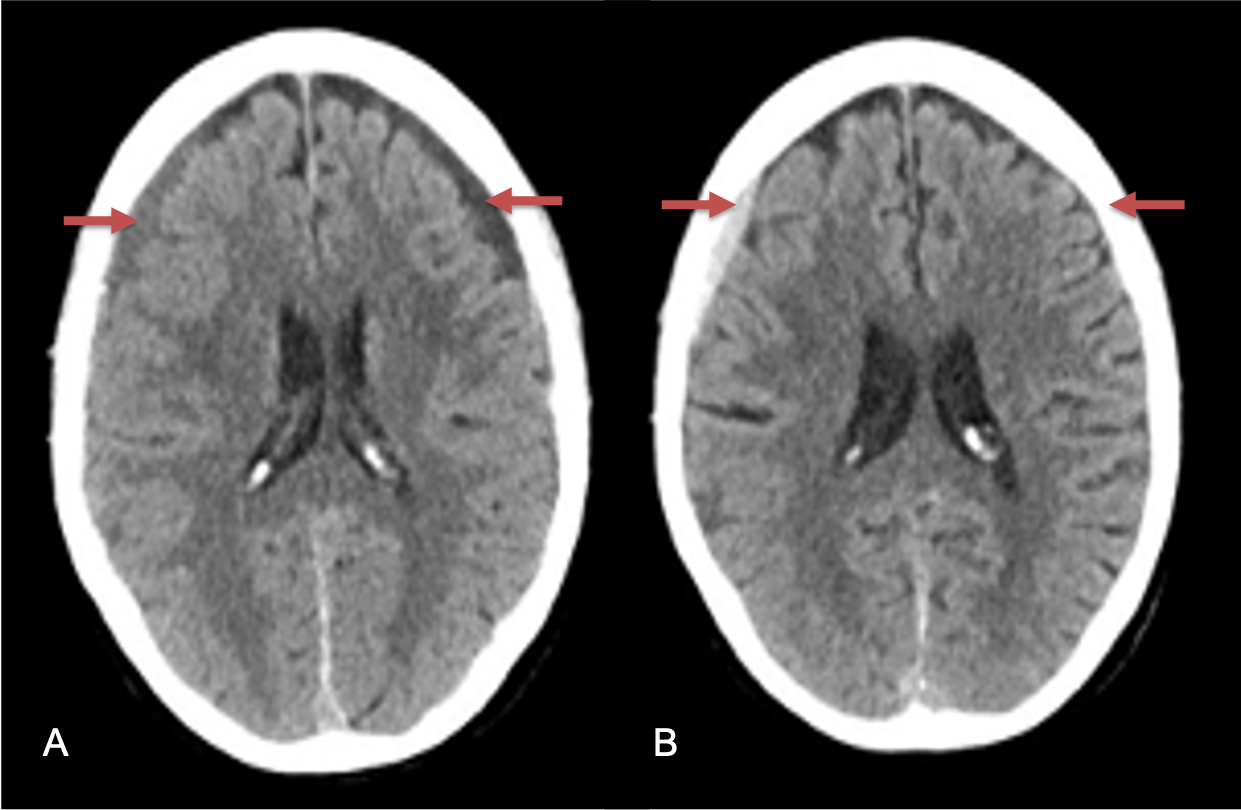

Clinically, the patient improved over the few weeks with the occasional transient twinge of a headache, but resolution of dizziness. Follow-up CT at 10 weeks demonstrated complete resolution of the bilateral subdural hematomas with our patient complete symptomatic and back to all of his activities of daily living. Considering his history of thrombocytopenia and CLL, we will continue to monitor him into the future and are excited about his progress and recovery. (Figure 4. A and B)

Figure 4. A and B) – 10 weeks following embolization demonstrates complete resolution of bilateral collections both acute and chronic.